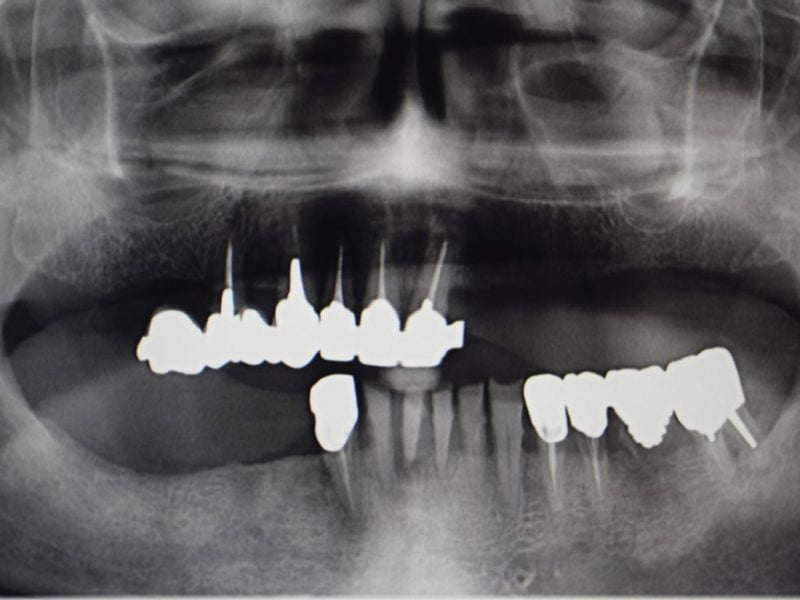

• Age: 65

• Sex: Male

• Smoker: Yes

• Pathologies: None

• Hygenic state: Very bad

• Alergies: None

The use of an arch to help praparing the ostheotomy in terms of inclination and positioning can be a great option to easily define the correct positionin for an all on four concept. This patient came with the request of stabilizing his own prosthesis so the treatment plan included the insertion of 4 implants on which we will use the suitable straight and angulated MUA to stabilize a retentive bar to retain a duplicate of the pre-existing prosthesis.

During the surgical session the preparation of the implant sites was made with the help of the guide arch that have to be inserted in the medial area and gives the indication on the correct positioning of implants for an all on four or all on six concept prosthesis. To minimize the tissue trauma we inseted the implants with a flapless surgery and with the use of stops to determine precisely also the lenght of the preparation. Right after the surgery the patient was left with healing screws on top of the implant and with his previous denture which we hollowed internally to avoid trauma on the implants. After 5 months the patient came back we took an impression an made a duplicate of the prosthesis which we used to build the bar to fix on top of MUAs and an internal framework and the retentive caps.

The guide allows to easily determine the inclination of the preparating tools but this also helps also the choice of the angled MUA. During the second session we simpli inserted the Multi unit abutments and fixed the prosthetic bar with the proper screws before trying and checking the occlusion of the definitive prosthesis.